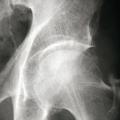

La forme pseudorhumatoïde est rare (5 %), simulant une polyarthrite rhumatoïde. L’arthrite chronique à PPC se présente comme une oligo- ou une polyarthrite, avec parfois des signes systémiques d’inflammation (élévation de la vitesse de sédimentation et de la protéine C-réactive [CRP]). La superposition d’accès aigus microcristallins est évocatrice de ce diagnostic. Il s’agit d’un diagnostic différentiel de polyarthrite rhumatoïde du sujet âgé ou de pseudopolyarthrite rhizomélique. Le diagnostic repose sur la mise en évidence des cristaux de PPC, même si les radiographies standard sont évocatrices. L’atteinte radiographique associe des calcifications des cartilages articulaires (fig. 7) et des fibrocartilages (fig. 8, 9, 10 et 11) [à rechercher systématiquement sur les radiographies de poignets, genoux et symphyse pubienne]. La mise en évidence d’une chondrocalcinose sur des radiographies standard renforce le diagnostic de rhumatisme à PPC mais l’absence de dépôts calciques ne l’élimine pas (la sensibilité de la radiographie standard étant imparfaite). L’échographie peut mettre en évidence des dépôts de PPC, qui apparaissent comme une fine bande hyperéchogène au sein des cartilages hyalins et comme des points scintillants dans les fibrocartilages ou dans la membrane synoviale. La sensibilité de l’échographie est bien supérieure à celle de la radiographie standard. Le scanner peut également mettre en évidence des dépôts calciques évocateurs, notamment au niveau du rachis ou du bassin qui sont plus difficilement explorés par les radiographies et l’échographie.

Les arthropathies liées à l’arthrose ou destructrices ont une fréquence qui augmente avec l’âge. L’arthrose associée aux dépôts de PPC touche en particulier les genoux, avec une symptomatologie chronique et/ou des accès aigus cristallins. Par comparaison avec l’arthrose idiopathique, l’arthrose avec dépôt de PPC serait à l’origine d’une symptomatologie plus inflammatoire, toucherait des articulations inhabituelles (radiocarpienne, carpienne, gléno-humérale, médio-pied et arrière-pied, cheville) et serait associée à plus d’ostéophytes et de géodes. Cette arthropathie dégénérative peut s’accompagner de lésions structurales sévères avec disparition rapide de l’interligne (arthropathies destructrices : hanches, genoux, poignets, coudes) mimant une ostéo­arthropathie nerveuse.